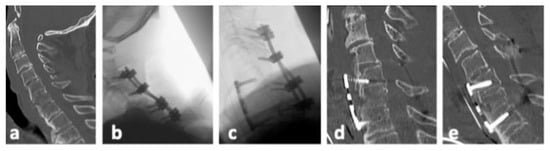

| No | Sex | Age | Level | Injury Type | Primary Treatment | Therapy of Secondary Dislocation |

|---|---|---|---|---|---|---|

| 1 | f | 91 | C6/7 | B2 | ACDF C6/7 with plate and iliac crest graft | Posterior instrumentation C5/6/7/Th1 |

| 2 | f | 74 | C5/6 | B2 | ACDF C5/6 with plate and iliac crest graft | Removal of plate and ACDF C5/6/7 with plate |

| 3 | m | 78 | C6/7 | B3 | Posterior instrumentation C3/4 to C6/7 andAnterior fixation C5 to C7 with plate | Posterior instrumentation C3/4/5/6/7Anterior fixation C5 to C7 with plate |

| 4 | m | 82 | C5/6 | B3 | ACDF C5/6 with plate and iliac crest graft | Posterior instrumentation C3/4/5/6/7 and ACDF C4/5/6/7 with plate and intervertebral cages |

| 5 | m | 66 | C6/7 | B3 | ACDF C5/6/7 with plate and iliac crest grafts | Halo fixator |

| 6 | f | 80 | C6/7 | C | ACDF C6/7 with plate and allogenous bone graft | Posterior instrumentation C4/5 to Th1/2 |

| 7 | f | 70 | C6/7 | C | ACDF C6/7 with plate and iliac crest graft | Posterior instrumentation C3/4/5 to Th1/2 |

| 8 | m | 68 | C6/7 | C | ACDF C6/7 with plate and iliac crest graft | Posterior instrumentation C6/7/Th1/2 |

| 9 | f | 74 | C6/7 | C | ACDF C5/6/7 with plate and intervertebral cages | Posterior instrumentation C5/6/7/Th1 |

| 10 | m | 79 | C6/7 | C | ACDF C6/7 with plate and iliac crest graft | Posterior instrumentation recommended; patient refused |

| 11 | f | 67 | C5/6 | C | ACDF C5/6 with plate and intervertebral cage | Posterior instrumentation C4/5/6/7 |